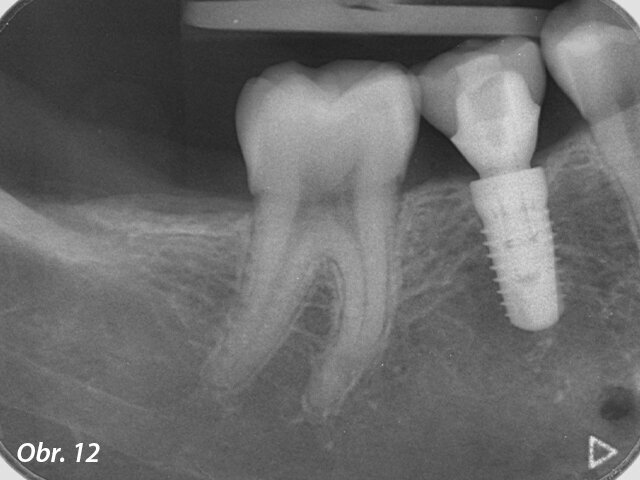

Po třech měsících byl na implantát umístěn skenovací abutment a zhotoven intraorální sken situace přístrojem Planmeca Emerald za účelem navržení korunkové náhrady.